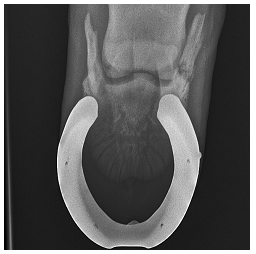

Caso clínico: Equino Quarto de Milha de vaquejada, 12 anos, claudicando grau 3 de membro torácico direito. Ao exame clínico apresenta extrema sensibilidade ao uso da tenaz de casco na região dos talões e na palpação manual na região palmaromedial e palmarolateral, ligeiramente proximal à região coronária. Ao bloqueio anestésico com 5 mL de lidocaína 2% em cada nervo digital palmar, paciente cessa claudicação após 15 minutos. O exame radiográfico foi realizado com ferraduras (não indicado), obtendo a imagem abaixo.

Considerando o diagnóstico obtido através do bloqueio anestésico e imagem radiográfica, qual a possível causa da claudicação, ferrageamento terapêutico e tratamento paliativo, respectivamente?